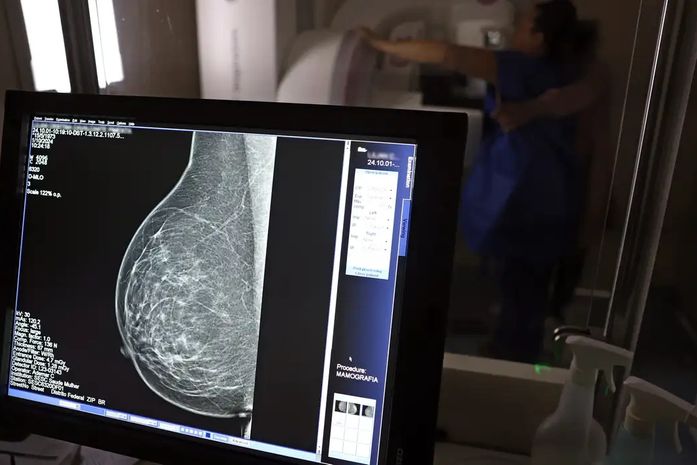

No Outubro Rosa, o Instituto Nacional de Câncer (Inca) estimou 73.610 novos casos este ano no país. É o câncer que mais mata mulheres no Brasil. As mulheres em tratamento pela doença têm o direito de receber o auxílio-doença ou o benefício de prestação continuada.

A vice-presidente da Comissão de Previdência Social Pública da Ordem dos Advogados do Brasil do Rio de Janeiro (OAB-RJ), Danielle Guimarães, destaca que o câncer de mama é uma das doenças que mais afetam mulheres no Brasil, impactando não apenas a saúde física e emocional, mas também a capacidade de trabalho e a segurança financeira das pacientes.